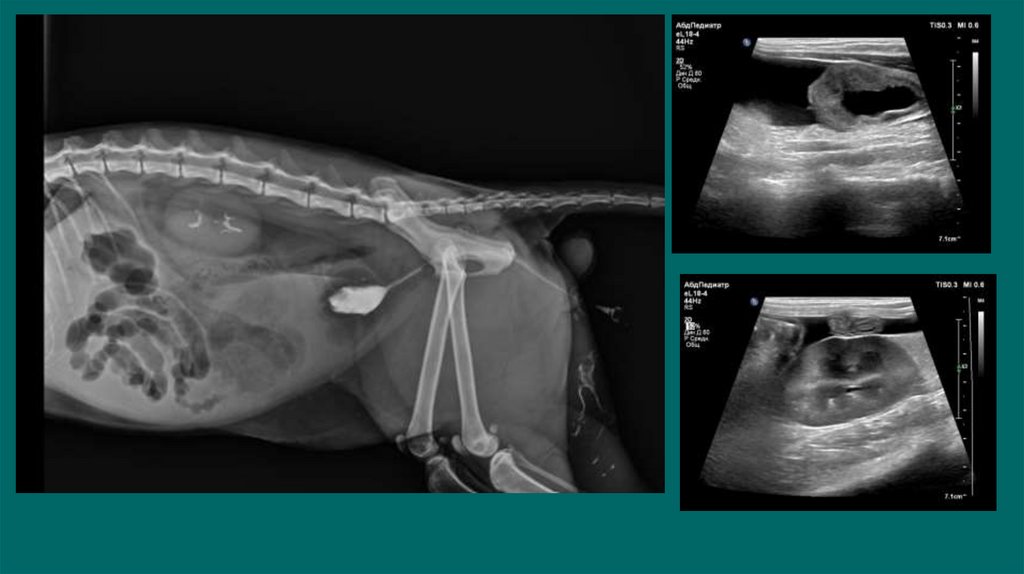

Рентгенологические исследования

Позитивно-контрастная цистоуретрограмма

Ультразвуковое исследование

6. Рентгенологические исследования

Размер и симметричность почек, размер и топографию мочевого пузыря, размер и

положение репродуктивных органов.

У собак почки имеют бобовидную форму. Размер в 2,5-3,5 раза превышают длину L 2

У кошек овальная до круглой. Размер почек измеряют на ВД проекции в 2,4-3,0 раза

превышают длину L2

Размер проксимального отдела мочеточника :

Собаки 2-3мм. Кошки 1-2мм

Метод выявления рентгеноконтрастных уролитов (фосфат кальция, оксалат кальция,

струвиты)

Ураты /цистеиновые уролиты рентгенопрозрачны.

7.

8. Диагностика

9.

10.

11.

12.

13. Позитивно-контрастная цистоуретрограмма

Показания:

Определение размера, формы и расположения мочевого пузыря

Определение проходимости или разрыва мочевого пузыря или уретры.

Обнаружение дефектов наполнения, связанных с уролитами (цистины/ураты) или гематомами,

выявления полипов или новообразований.

19. Ультразвуковое исследование

Можем обнаружить рентгенпрозрачные уролиты ,оценивать архитектуру

почки, паранефральные ткани, ретроперитониальные ткани, кисты

,инфартуи ы почек, изменение эхогенности, неоплазию, расширение

почечных лоханок и мочеточников, измерить толщину стенки мочевого

пузыря, визуализировать свободную жидкость в брюшной полости

УЗИ мониторинг изменений картины мочевой системы

• размер уретры

• размер лоханки и мочеточников

• количество свободной жидкости